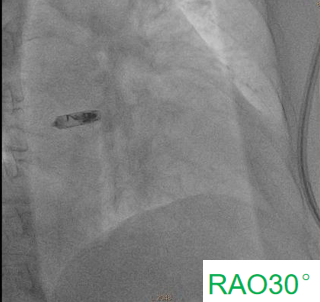

术中,医疗团队经穿刺右侧股静脉建立静脉通路,随后使用猪尾导管分别在RAO30°& LAO30°进行右心耳造影,清晰获取右心耳结构及目标植入位置,最终成功于右心耳基底部植入心房无导线起搏器,手术全程顺利。术后患者各项参数稳定,恢复良好,次日便出院,真正实现了“介入操作、快速康复”。